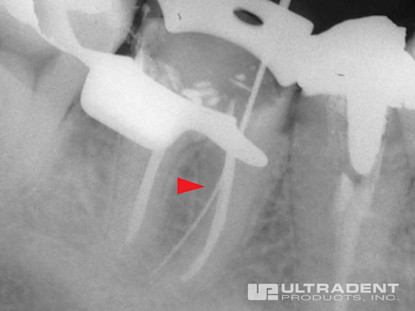

Etkili Perforasyon Onarımı

Mesial bukal kanalın servikal üçüncü kısmında yer alan perforasyon.